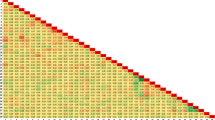

Moreover, we calculated correlation between the factors. The relationship between these features is depicted in the correlation matrix. This correlation was better illustrated by the heat map. Evaluating the potential correlations between the features, the Pearson function with threshold 0.85 was used. The Pearson correlation coefficient can also be used to assess whether two variables have a significant relationship or not [33]. The corresponding cell is red if there is a strong correlation (greater than a threshold) between two features. The outcomes demonstrated that there is little correlation between the predictive features. The correlation of two features is indicated by the value inside each cell (refer to Fig. 4). According to the Fig. 4 characteristics such as age, OTS, Grade VA, and type are some of the essential features in OGI patients. To determine the clinical factors’ significance for the research, a random forest ranking is employed (Fig. 3). The most illuminating set of features can be chosen by plotting the random forest’s interpretation of feature importance. It selects many possible combinations of variables to find the best features [34]. Python 3.8 was used to draw all the figures.